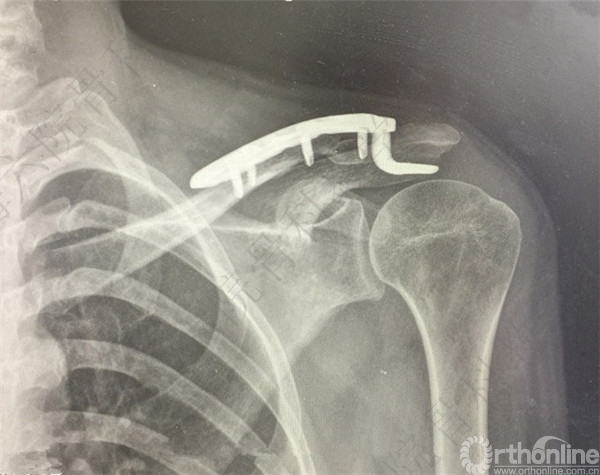

患者择期行左锁骨远端骨折切开复位内固定术。

术后X线摄片示:骨折对位对线可。

患者术后复查,X线摄片示:骨折端对位对线欠佳,远端骨块向前下方移位。

患者取出内固定,X线摄片示,骨折端畸形愈合,对位对线欠佳。

医方在复查期间未注意X线摄片显示的远端骨折移位,行取出内固定术前未充分告知患者。医方存在漏诊,手术指证掌握不当,术后并发症观察、处理不当,告知缺陷等过失。